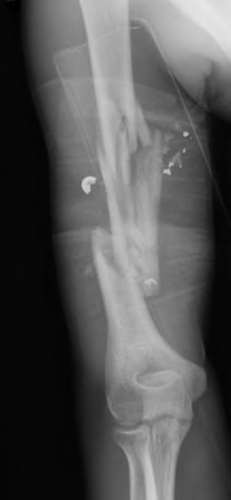

A 20-year-old park ranger trips and falls onto his right wrist with the wrist in extension and pronation. The local urgent care orders both radiographs and a CT, which you review and determine to be normal. The patient complains of ulnar-sided wrist pain. On exam, his tenderness is localized to the fovea. Ulnar deviation also causes him pain. There is no snapping sensation with wrist supination, flexion, and ulnar deviation. He otherwise has 5/5 strength to his first dorsal interosseous muscle with 4mm static two-point discrimination on the ulnar side of the 4th digit. Which of the following injuries is most likely responsible for his symptoms and exam?